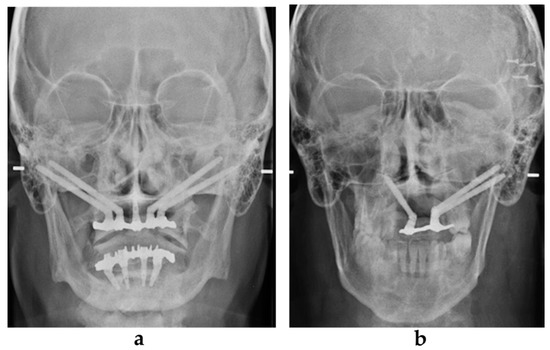

2.4. Prosthetic Procedure

After the flap closure, a sterilized rubber dam perforated at the position of the already mounted transfers was set up. The resin template that was already used for the CBCT was drilled on the palatal side to allow the placement of the transfers. The screw-retained transfers were splinted together using inlay pattern resin (Duralay, Reliance, Worth, TX, USA) The resin template was also used as an impression tray. The impression was made using polyether material injected through the free spaces using a carrier syringe. Very short transfers were chosen to keep the template (reproducing the previously evaluated prosthesis) in occlusion during the setting of the impression material. After transfer removal, healing abutments were positioned onto the implant connections and the impression tray was sent to the technician. After 48 h, a metal framework with the front teeth and the occlusal plate in position was evaluated intraorally. After 72 h, the final provisional screw-retained prosthesis was evaluated intraorally and delivered. In some cases, where the framework check was incorrect, the prosthesis delivery was delayed by approximately 120 h. In addition, radiographic evaluation was performed after loading (Figure 3a,b).

Figure 3. Post-loading radiographic evaluation in a patient with maxillary atrophy (a) and in an oncologic patient (b).